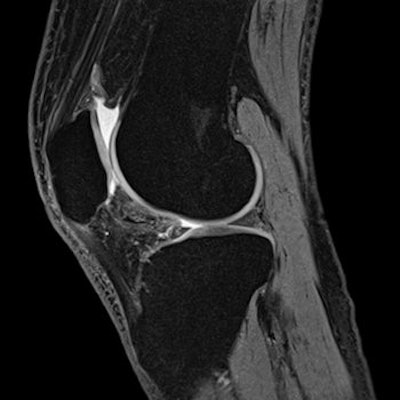

The researchers used a 1-tesla open MR system to exam 24 knees of 20 morbidly obese patients, with a mean age of 14.2 years, and found that a cartilage lesion could be detected in at least one region of the knee in all the pateints. They also identified retropatellar cartilage lesions in 19 knees. In the lateral compartment of the knee, 10 grade I cartilage lesions and four grade II cartilage lesions were described whereas the medial compartment showed eight grade I cases, 13 grade II cases, and two grade III cases. Meniscal changes also were assessed in most patients.

| Knee MR image shows a tear in the meniscus. It was performed on a 1.5-tesla Magnetom Essenza system. Image courtesy of Siemens Healthcare. |

"The present study demonstrates for the first time that in morbidly obese children and adolescents, who suffer from pains in their knees, marked morphological changes of the cartilages from different grades and in different compartments could be detected," the authors wrote.

The defects are similar to those found in victims of various accidents or "immediate sequelae of traumatic influences, which can be found in older people due to mechanical injuries or as an inflammatory response to their joints," they noted. So far these changes had not been found in young patients without any traumatic history or severe disease that could cause the knee cartilage damage.